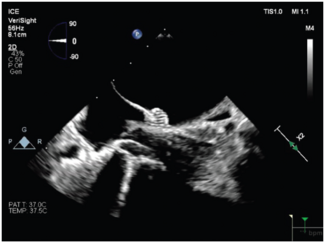

Jason Chinitz, MD discusses the central role of ICE in advancing procedural safety, efficiency, and operator control—spanning fluoroless AF ablation, LAAO, and concomitant procedures.

This report describes a successful single-procedure use of pulsed field ablation and left atrial appendage occlusion, guided entirely by intracardiac echocardiography, as a potential one-stop approach to complex AF management.